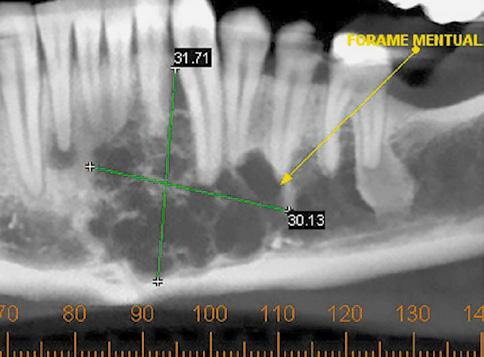

Paciente do sexo masculino, 22 anos de idade, procurou o Serviço de Cirurgia e Traumatologia Bucomaxilofacial do Hospital das Clínicas da Universidade Federal de Minas Gerais, para avaliação de lesão assintomática em mandíbula. Ele relatou ausência de sintomatologia álgica, parestesia, hipoestesia ou disestesia, e não apresentava comorbidades. Ao exame físico extrabucal e intrabucal, não foram detectadas alterações dignas de nota (Fig. 1A). Entretanto, o exame tomográfico revelou extensa imagem hipodensa na região de sínfise e corpo esquerdo de mandíbula, multiloculada, com aspecto de destruição e expansão óssea, e associada aos dentes 31, 32, 33, 34, 35 e 41 (Fig. 1B). Uma biópsia incisional confirmou a hipótese diagnóstica de AM convencional (Fig. 1C). Por meio de um acesso cirúrgico intrabucal e sob anestesia geral, o tumor foi removido através de uma ressecção marginal mínima da mandíbula, com margem de segurança óssea variando entre 5 e 10 mm, preservando a borda inferior mandibular, e exodontia dos elementos associados, além do dente 42 (Fig. 1D). Terapias coadjuvantes, como ostectomia periférica em toda extensão da lesão e aplicação de solução de Carnoy (3ml de clorofórmio, 6ml de álcool absoluto, 1ml de ácido glacial acético e 1g de clorito férrico), durante 5 minutos, foram realizadas em toda loja cirúrgica. Após um período de 4 anos de controle pós-operatório, com consultas trimestrais no primeiro ano, semestrais no segundo, e anuais a partir do terceiro ano, não foram observados, em exames clínicos e de imagem, sinais de recidiva da lesão. O paciente foi, então, submetido a um procedimento de reconstrução mandibular, que consistiu na colocação, por meio de um acesso cirúrgico extrabucal (submentoniano), de um enxerto livre autógeno de crista ilíaca, fixado com placas de titânio do sistema 2.0 (Fig. 2). Transcorridos cinco meses da enxertia, a região foi reabilitada por meio de uma prótese dentária implantossuportada, utilizando-se quatro implantes: três implantes plataforma Cone Morse de 3,75 mm de diâmetro por 13 mm de comprimento, na área enxertada; e um implante na posição de molares, plataforma Cone Morse, de 5 mm de diâmetro e 11 mm de comprimento (Fig. 3A e 3B). Após nove anos da cirurgia para a ressecção tumoral, observou-se ausência de sinais de recidiva e o paciente encontrava-se satisfeito com o resultado do tratamento (Fig. 3B e 3C).

Figura 1: A) Aspecto intrabucal pré-operatório, evidenciando aspecto de normalidade. B) Tomografia computadorizada mostrando uma imagem hipodensa, bem delimitada, multilocular, em região de sínfise e corpo esquerdo de mandíbula. C) Lesão composta por ninhos e cordões de células epiteliais odontogênicas com padrão de crescimento sólido. Individualmente, as células epiteliais, na periferia, eram colunares, hipercromáticas, dispostas em paliçada e semelhantes a ameloblastos. Na porção central, as células tinham disposição frouxa, semelhante ao retículo estrelado do órgão do esmalte. Nota-se, em áreas focais, degeneração cística. O estroma foi representado por tecido conjuntivo fibroso e pouco vascularizado. D) Ressecção marginal da mandíbula, com preservação do osso basilar.

Figura 3: A) Aspecto intrabucal após reabilitação com implantes. B) Tomografia computadorizada mostrando implantes instalados e ausência de recidiva, após nove anos da ressecção do tumor. C) Corte axial mandibular nove anos após ressecção do tumor, evidenciando ausência de recidiva. DISCUSSÃO